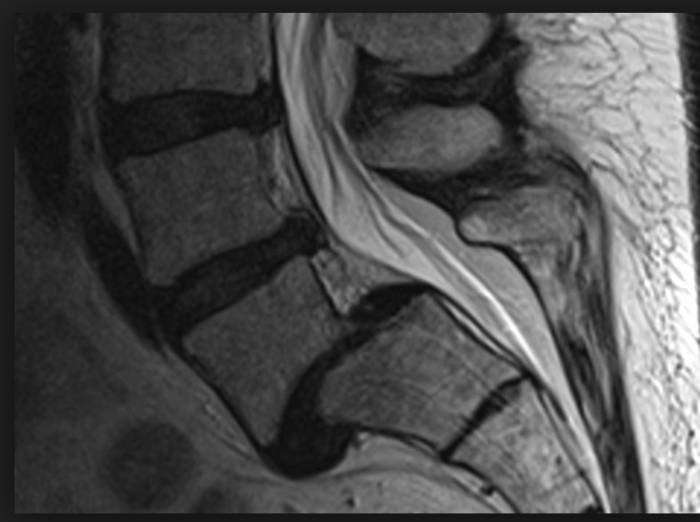

Спондилолистез на МРТ

Особенности диагностики

Определять, какой именно способ лечения смещения позвонков подойдет лучше, должен только врач-ортопед или травматолог, поэтому при появлении первых подозрительных признаков нужно обращаться к специалисту для проведения диагностического обследования. К основным диагностическим процедурам относятся:

- спондилография;

- компьютерная томография (КТ);

- рентген поясничного отдела позвоночника с функциональными пробами;

- магнитно-резонансная томография (МРТ);

- пальпация и визуальный осмотр.

Диагностика заболевания

С помощью всех вышеперечисленных мероприятий врач сможет определить локализацию поражения позвоночника, ее характер и степень. Также это позволяет установить сопутствующие защемления нервов. Разумеется, при постановлении диагноза обязательно нужно учитывать клинические проявления, на основе которых и составляется курс терапии.